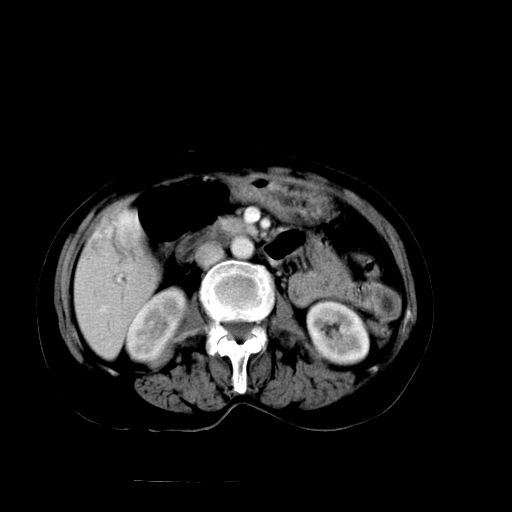

以下是引用随光逐影在2009-4-7 8:21:00的发言:[br]肝内外胆管多发性结石并肝内外胆管扩张;胆系感染。